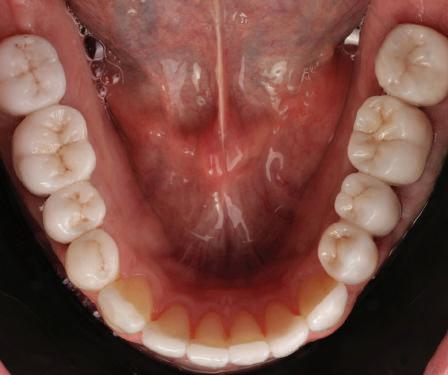

20 Dental Tribune Bulgarian Edition / октомври 2022 г. П ациентите със завършен растеж и скелетни проблеми обикновено представляват предизвикателство за ортодонт ската практика. Необходимостта от изваждане на зъби в комбинация с особеностите на възрастовата ортодонтия изисква особено внима ние. Фокусът върху критично важното значение на позицията на долните резци във връзка с дългосроч ната стабилност и постигането на оптимални оклузални взаимоотношения при затварянето на екстракционните пространства лесно може да излезе извън контрол. Когато към тези чисто кли нични проблеми се добави и стресът от натоваре ната практика, предизвикателството става още по-голямо. Всички тези фактори налагат използ ването на доказан подход с ясни и последовател ни стъпки, в което се разкрива силата на дисциплината „Алекзандър“ – предвидим протокол през целия процес на елиминиране на ротациите, ниве лиране на дъгите, затваряне на екстракционните пространства и финализиране на случая. Именно такъв е и случаят, който презентираме –екстракционен, скелетен клас 3 при възрастен па циент, лекуван по системата „Алекзандър“. ПРЕДВИДИМИ РЕЗУЛТАТИ ПРИ ПАЦИЕНТИ СЪС ЗАВЪРШЕН РАСТЕЖ И СКЕЛЕТЕН КЛАС 3, ИЗПОЛЗВАЙКИ ЕКСТРАКЦИОННО ЛЕЧЕНИЕ ПО ДИСЦИПЛИНАТА „АЛЕКЗАНДЪР“ Д-р Радой Димитров, България Преди започване на лечение клиничен случай | ортодонтия Фиг. 1а–1e Преди започване на лечение. Пациентът пристига в практиката с основното оплакване от невъзмож ност за нормално дъвчене. Снета е цялата необходима диагностична ин формация. Фиг. 1f–1h Снимки в профил и анфас. Фиг. 1i–1k Панорамна снимка, телерентгенография и анализ на телерент генография. Фиг. 1а Фиг. 1d Фиг. 1f Фиг. 1g Фиг. 1h Фиг. 1e Фиг. 1b Фиг. 1c Фиг. 1i Фиг. 1j Фиг. 1k

closed.

21Dental Tribune Bulgarian Edition / октомври 2022 г. ДИАГНОСТИЧНИ РЕЗУЛТАТИ: 1. Възраст на пациента: 21 години 2. Скелетен клас III (ANB 0) 3. Зъбен клас 3 4. Ръбцова захапка във фронта, кръстосана в дисталните участъци 5. Тясна горна челюст 6. Overjet – 0 мм, Overbite – 0 мм 7. Несъответствие на горната с долната средна линия 8. Единични контакти в ЦО 9. Хиподивергентен тип на растеж SN/MP – 33.5 10. Неравен гингивален контур 11. Неравна линия на усмивката 12. Тенденция за рецесии в долен фронт ПРЕПОРЪЧИТЕЛНО ЛЕЧЕНИЕ: Пълно ортодонтско лечение с метални брекети „Алекзандър“ Корекция на клас 3 захапката в областта на кучешките зъби с екстракция на първите пре молари в долна челюст Корекция на кръстосаната захапка в дистални участъци Коригиране на ръбцовата захапка във фронта Подобряване на ОJ и OB на пациента Стрипинг в долен фронт Подреждане на зъбите в горната и долната челюст Професионално хигиенизиране и профилактични дентални прегледи са препоръчителни на всеки 6 месеца. 1-ви месец След 1 месец са залепени брекети в горната челюст – поставена е еластична дъга. 016 NiTi. В долната челюст са елиминирани ротациите, поставена е стоманена дъга. 016SS, закалена с ток, и еластична верижка за затваряне на пространствата. 3-ти месец В долната челюст е поставена трета дъга – 17 x 25 NiTi с къси лигатури и верижка

В горната челюст се затварят пространствата с дъга .016SS и верижка. 5-и месец На 5-ия месец след залепяне на брекетите в долната челюст е поставена стоманена дъга 16 x 22 SS с четвъртито сечение, омега луп и тай бек. В горната челюст е поставена дъга 17 x 25 NiTi. Поради липсата на стабилни оклузални контакти са поставени лингвални верижки в областта на моларите, за да се предотврати нежелана ротация на 7-ите зъби. 6-и месец На 6-ия месец от началото на лечението са екстрахирани долните първи премолари, поставена е дъга 16 x 22 SS със затваряща чупка teardrop. Чупката се активира всеки месец по 1 мм с чинч-бек. клиничен случай | ортодонтия СТЪПКИ НА ЛЕЧЕНИЕТО Начало на лечението Лечението започва с поставяне на апарат за бърза експанзия в горната челюст. През първия месец от лечението са направени 24 оборота на апарата за експанзия. Залепени са брекети в долната челюст, поставена е дъга 17x25 CuNiTi, като са предпи сани клас 3 ластици (1/4”,4 1/2 oz) по време на сън, за да се осигури контрол върху торка на долните резци. Фиг. 2а Фиг. 3a Фиг. 4a Фиг. 3b Фиг. 4b Фиг. 3c Фиг. 4c Фиг. 3d Фиг. 4d Фиг. 3e Фиг. 4e Фиг. 5a Фиг. 5b Фиг. 5c Фиг. 5d Фиг. 5e Фиг. 6a Фиг. 6b Фиг. 6c Фиг. 6d Фиг. 6e Фиг. 7a Фиг. 7b Фиг. 7c Фиг. 7d Фиг. 7e Фиг. 2b Фиг. 2c Фиг. 2d

Dental Tribune Bulgarian Edition / октомври 2022 г.22 клиничен случай | ортодонтия 14-и месец В горната и долната челюст са поставени последни стоманени дъга с омега луп и тай бек – 17 x 25 SS с четвъртито сечение. Назначени е ластик за средната линия в комбинация с клас 3 ластик (1/4”, 6 1/2 oz). Контролни рентгенографии 13-и месец Екстракционните пространства са затворени. Направена е контролна панорамна снимка за оценка позицията на корените. Взето е решение за презалепване на брекетите на 12, 22 и пръстените на 36 и 46. 21-ви месец Средната линия в горната и долната челюст съвпадат. Ластиците са спрени. Свалени са пръстените и брекетите в горната и долната челюст, зигзаг ластици не са използвани поради благоприятните оклузални взаимоотношения. Фиг. 11j Ортопантомография в края на лечението. Фиг. 11k Телерентгенография след края на лечението. Фиг. 11l Анализ на телерентгенографията след лечението. Фиг. 11m Последователност на дъгите в горната и долната челюст Фиг. 11n Суперимпозиция на PreOp и PostOp ортопантомографии. 10-и месец Затварянето на пространствата е предвидимо и контролирано, без да се отварят пространства в зъбната дъга. Фиг. 8a Фиг. 8b Фиг. 8c Фиг. 8d Фиг. 8e Фиг. 10a Фиг. 10b Фиг. 10c Фиг. 10d Фиг. 10e Фиг. 9a Фиг. 9b Фиг. 9c Фиг. 9d Фиг. 9e Фиг. 9f Фиг. 11a Фиг. 11f Фиг. 11j Фиг. 11l Фиг. 11m Фиг. 11n Фиг. 11k Фиг. 11g Фиг. 11h Фиг. 11i Фиг. 11b Фиг. 11c Фиг. 11d Фиг. 11e

Dental Tribune Bulgarian Edition / октомври 2022 г. 23клиничен случай | ортодонтия реклама Лечението е продължило 21 месеца. Проведено е домашно избелване с индивидуални шини. За автора: Д-р Радой Димитров завършва с отличие Факултета по дентална медицина към МУ–София през 2015 г. В продължение на 5 години работи в няколко водещи практики в София, като през 2019 г. заедно със своята съпру га д-р Траяна Димитрова основават собствена практика в гр. Гоце Делчев –Dimitrovi Dental Care. Посещава редица курсове за повишаване на квалификаци ята, но най-сериозен тласък в развитието на ортодонтската си практика получава след завършването на комплексната ортодонтска програма, воде на от д-р Иван Горялов, базирана на дисциплината „Алекзандър“ – система с повече от 50 години опит в целия свят. Д-р Димитров е член на Българския изследователски клуб „Алекзандър“. Взе ма участие като гост-лектор в симпозиума с международно участие The Power of the Alexander Discipline, който се проведе на 14–15.05.2022 г. С д-р Ди митров можете да свържете на тел. +359885 252 025. Заключение Представеният случай е ярък пример за възможностите и красо тата на дисциплината „Алекзандър“ – приложен е утвърден под ход с ясни правила и са постигнати очакваните цели. Резулта тът ще бъде дългосрочно стабилен, тъй като са спазени всички правила, които се отнасят към максимално комфортната пози ция на зъбите в края на лечението. Постигнати са красива усмив ка и стабилна оклузия. ПОСТИГНАТИ РЕЗУЛТАТИ ОТ ЛЕЧЕНИЕТО 1. Коригирана ръбцова захапка 2. Коригирана клас 3 захапка в областта на ку чешките зъби 3. Коригирана кръстосана захапка в дисталните участъци 4. Коригиран овърджет и овърбайт 5. Разширена е горната зъбна дъга 6. Подредени зъби в горната и долната челюст 7. Постигната е стабилна захапка с множество контакти в ЦО 8. Драматично е подобрена дъвкателната функ ция 9. Подобрена е линията на усмивката ДРУГИ ПРОВЕДЕНИ ДЕНТАЛНИ ПРОЦЕДУРИ 1. Домашно избелване на зъбите 2. Екстракция на мъдреците Фиг. 12a Фиг. 12b Фиг. 12c Фиг. 12eФиг. 12d Фиг. 12f Фиг. 12g Информация за дати, цени и отстъпки www.bracescourses.com 0889 22 55 01 Практически курсове лектор д-р Иван Горялов Дисциплината „Алекзандър“ ПЪТЯТ КЪМ СУПЕРУСМИВКИТЕ 100% връщане на цялата сума, ако не сте удовлетворени след преминаване на Ниво 1 Директно и индиректно залепяне на брекети Анализ, диагноза и план на лечение Лечение на клас 2 дълбока захапка Екстракционно лечение Лечение на клас 3 отворена захапка НИВО 5НИВО 1 НИВО 2 НИВО 3 НИВО 4